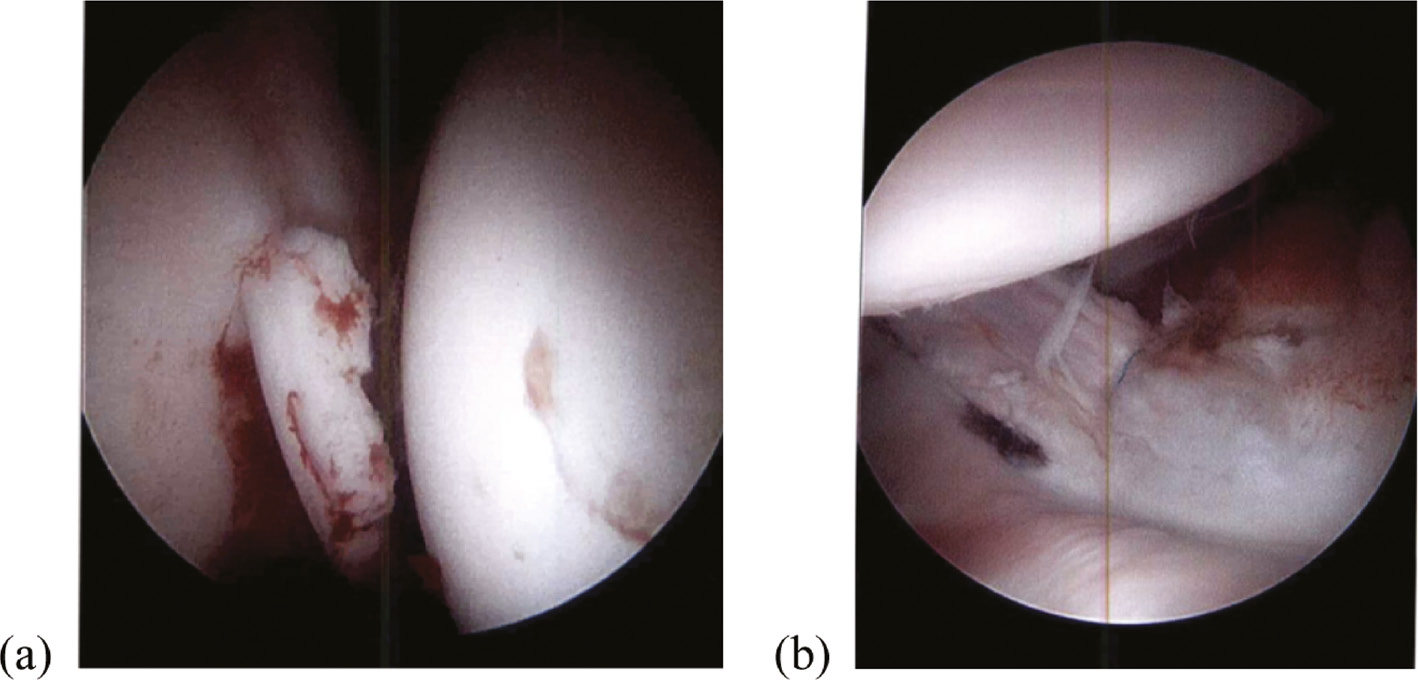

The indication for hip arthroscopy was an incarcerated fragment in four patients and an entrapped labrum with incongruent reduction in one patient. Arthroscopic procedures included loose body removal, labral repair, and acetabular microfracture in two patients, loose body removal and labral repair in one patient, and reduction of the entrapped labrum with debridement of the ligamentum teres in one patient. Mean operative time for arthroscopic cases was 105 minutes (range 80-134 minutes). Figure 4 demonstrates an intraarticular loose body and posterior labral repair. One operatively treated patient was from out-of-state and returned home for all clinical and radiographic follow-up. Among the other eight patients, mean clinical and radiographic follow-up was 16 months (range 2-36 months).

Figure 4. Intraoperative arthroscopy illustrating large chondral intraarticular loose body (a) and posterior labral repair (b).